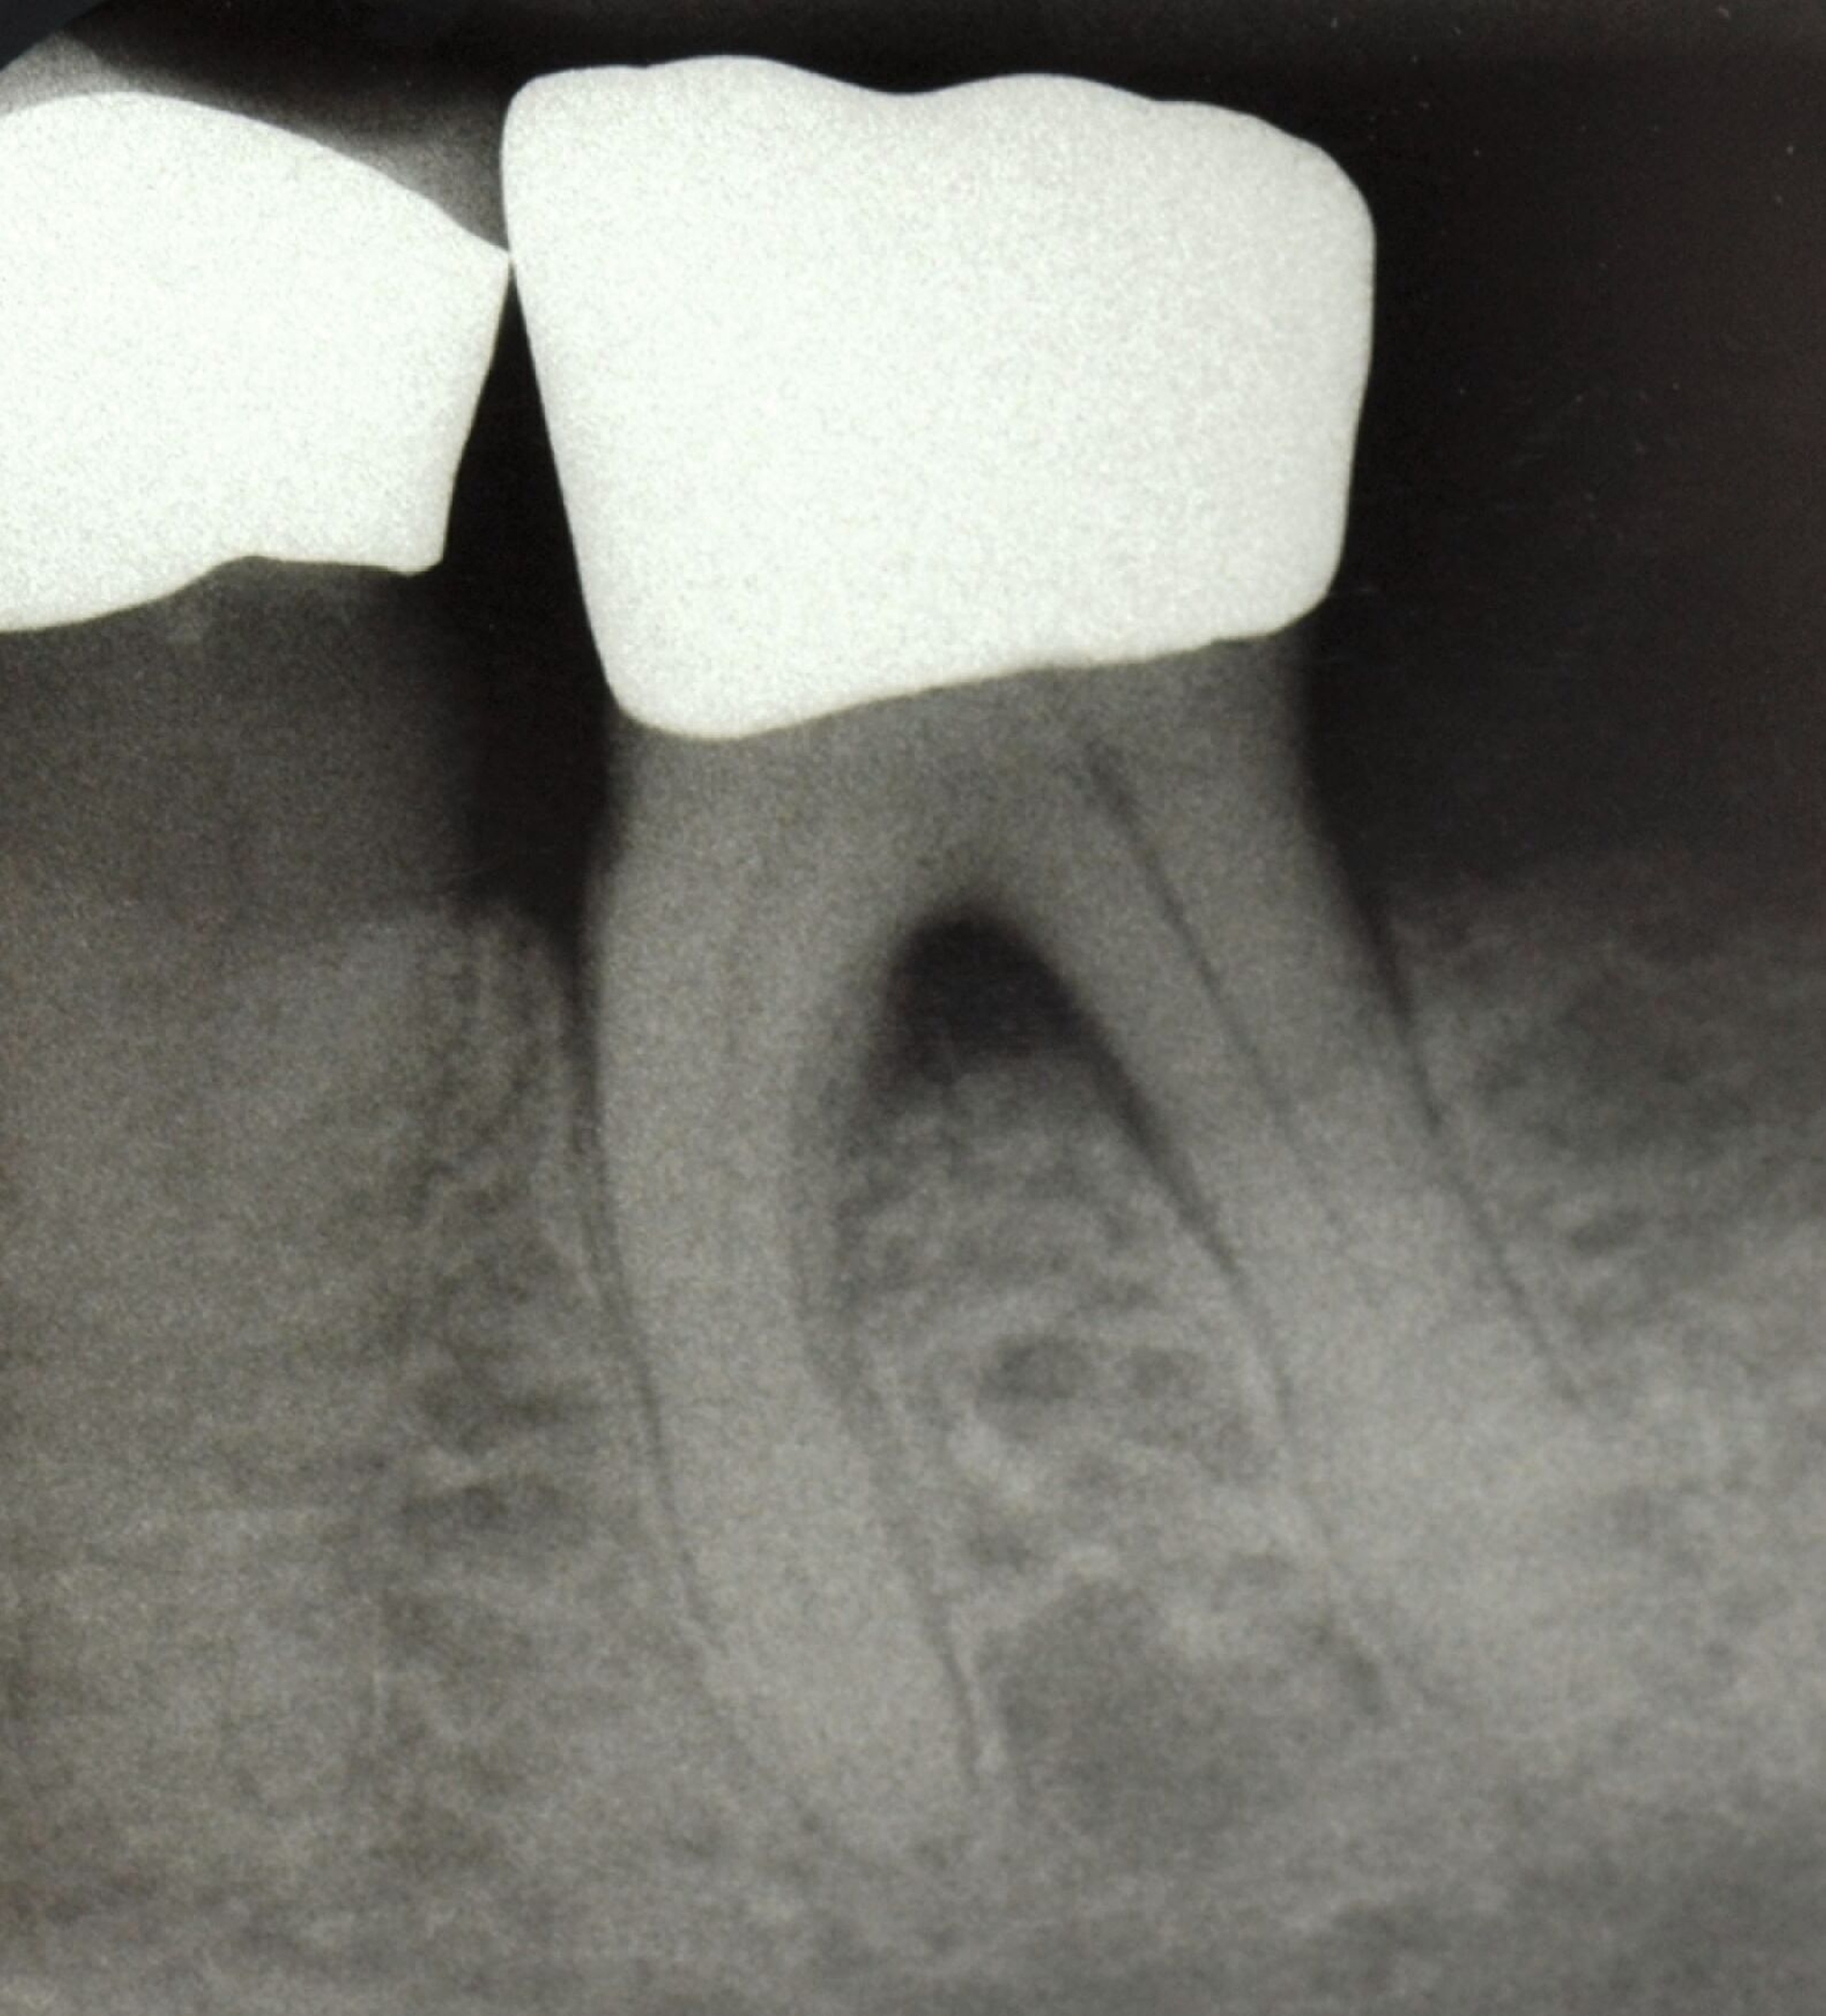

Ein adäquater Zugang zum Operationsbereich und auch für die zukünftigen Mundhygienemaßnahmen ist äußerst wichtig. Molaren mit Grad-II-Furkationsdefekten (mandibulär und bukkal maxillär) sind Kandidaten, die für ein regeneratives Verfahren infrage kommen. Basierend auf der verfügbaren Evidenz sind interdentale Grad-II-Furkationsdefekte an Oberkiefermolaren deutlich weniger geeignet, höchstwahrscheinlich aufgrund des eingeschränkten Zugangs. Weitere lokale Charakteristika können Auswirkungen auf die Ergebnisse der regenerativen Furkationschirurgie haben. Zum Beispiel können ein dickerer Phänotyp und das Fehlen einer Weichgeweberezession die Heilung nach GTR-Verfahren positiv beeinflussen. Günstigere Ergebnisse sind an Stellen zu erwarten, an denen das verbleibende approximale Knochenniveau koronal zum Eingang beziehungsweise zum Dach des Furkationsdefekts liegt, verglichen mit solchen, bei denen das approximale Knochenniveau auf der Höhe oder apikal des Furkationseingangs liegt. Ein enger interradikulärer Abstand kann eine gründliche Defektinstrumentierung beeinträchtigen. Das Vorhandensein einer Wurzelkanalfüllung ist nicht per se eine Kontraindikation für die Furkationsregeneration – vorausgesetzt, es gibt keine Anzeichen für apikale pathologische Veränderungen.